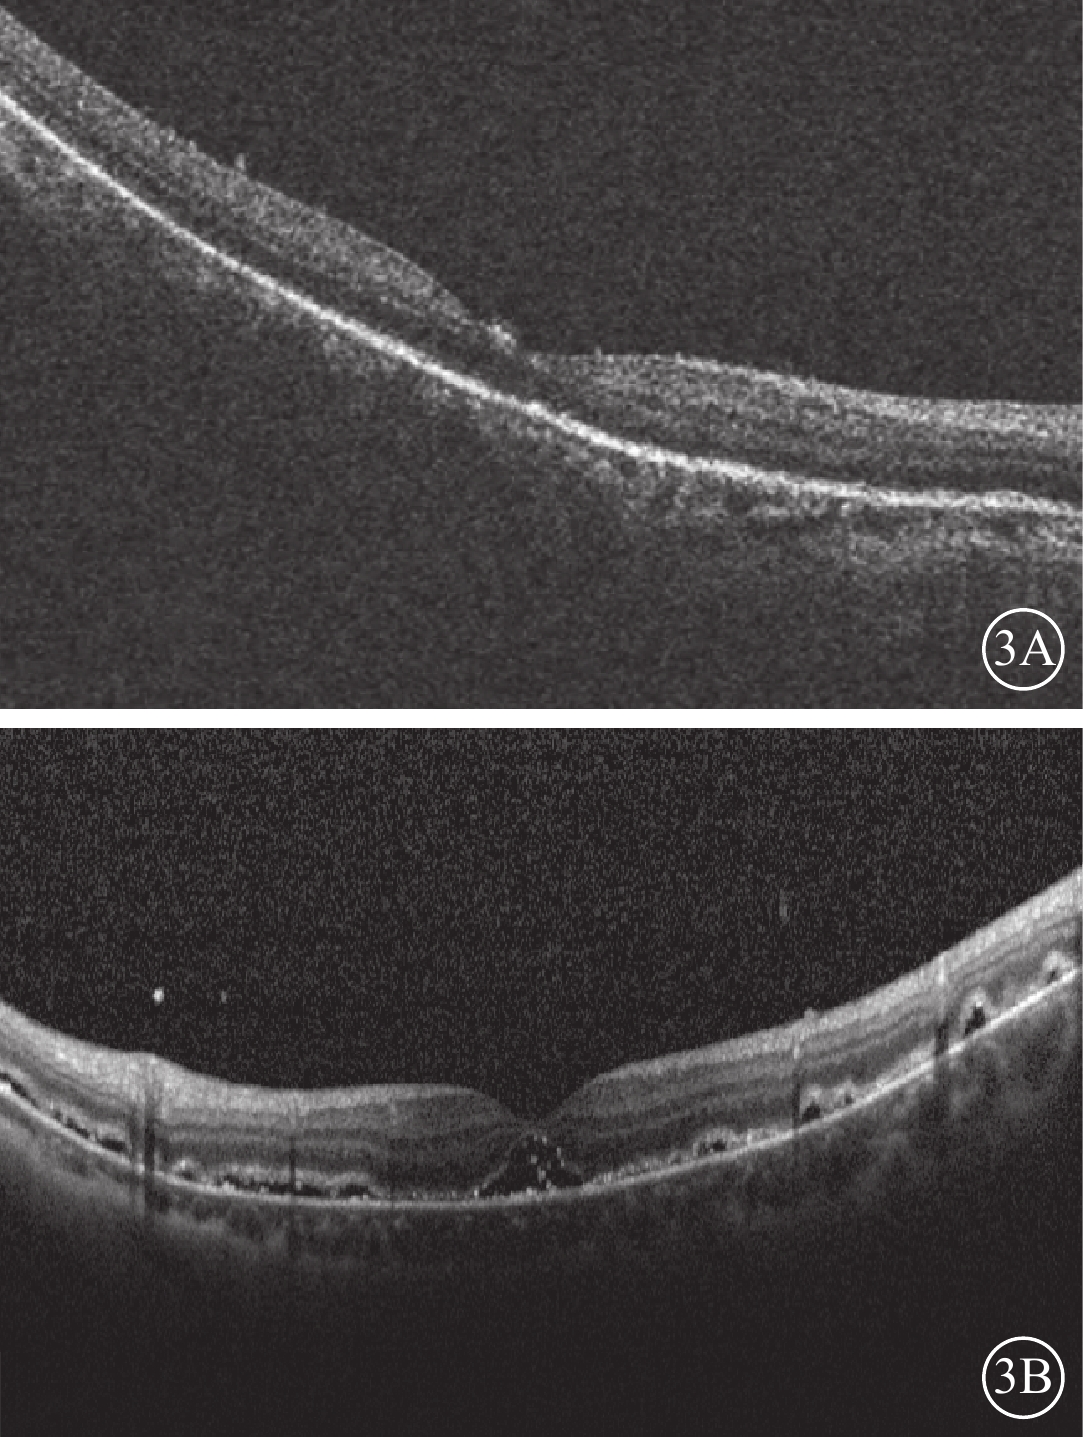

12只眼中,視網膜完全復位(圖3A)6只眼(50.00%),部分復位伴黃斑區視網膜下液(圖3B)4只眼(33.33%),未復位2只眼(16.67%)。視網膜部分復位伴黃斑區視網膜下液患眼原視網膜裂孔均位于脈絡膜墊壓嵴上,裂孔封閉;給予密切隨訪,視網膜下液隨時間延長逐漸吸收。視網膜未復位的2只眼均為高度近視眼,其中1只眼因脫離時間較長已形成3個裂孔且視網膜下見增生條帶,另1只眼為2 DD大小的馬蹄樣裂孔且視網膜脫離范圍累及4個象限;其采用玻璃體切割聯合硅油填充手術或鞏膜外硅膠墊壓手術復位視網膜。

圖3

患眼手術后1周OCT像。3A示黃斑區神經上皮完整復位;3B示視網膜部分復位,黃斑區視網膜下少許積液

圖3

患眼手術后1周OCT像。3A示黃斑區神經上皮完整復位;3B示視網膜部分復位,黃斑區視網膜下少許積液

12只眼中,視網膜完全復位(圖3A)6只眼(50.00%),部分復位伴黃斑區視網膜下液(圖3B)4只眼(33.33%),未復位2只眼(16.67%)。視網膜部分復位伴黃斑區視網膜下液患眼原視網膜裂孔均位于脈絡膜墊壓嵴上,裂孔封閉;給予密切隨訪,視網膜下液隨時間延長逐漸吸收。視網膜未復位的2只眼均為高度近視眼,其中1只眼因脫離時間較長已形成3個裂孔且視網膜下見增生條帶,另1只眼為2 DD大小的馬蹄樣裂孔且視網膜脫離范圍累及4個象限;其采用玻璃體切割聯合硅油填充手術或鞏膜外硅膠墊壓手術復位視網膜。

圖3

患眼手術后1周OCT像。3A示黃斑區神經上皮完整復位;3B示視網膜部分復位,黃斑區視網膜下少許積液

圖3

患眼手術后1周OCT像。3A示黃斑區神經上皮完整復位;3B示視網膜部分復位,黃斑區視網膜下少許積液